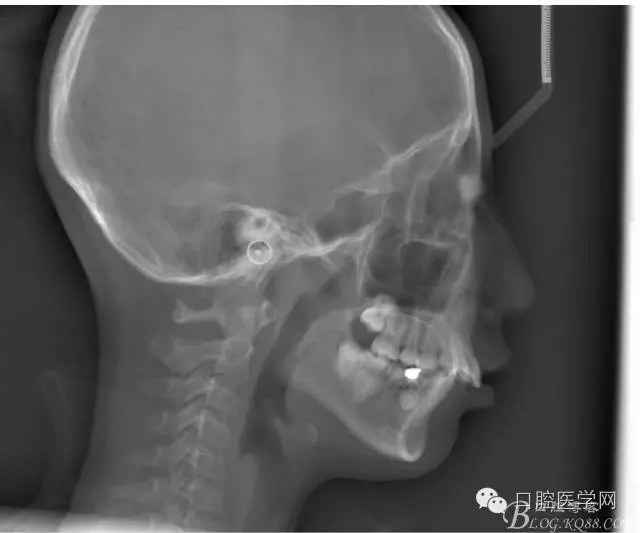

正畸前后頭顱側(cè)位SN平面和S點(diǎn)重疊圖:

正畸查:替牙合。第一恒磨牙中性合。上牙弓尖圓型下牙弓方圓型。前牙覆合3度覆蓋7.5mm。下前牙咬到上舌側(cè)牙齦。上頜擁擠4.0mm,下頜擁擠

3.0mm。上頜稍前突下頜后縮,上下唇前突,上前牙覆蓋下唇,下唇外翻。面下三分之一過(guò)短,頦唇溝明顯,開(kāi)唇露齒,頦饜窩明顯。顳下頜關(guān)節(jié)開(kāi)閉口無(wú)彈響,無(wú)壓痛,開(kāi)口型開(kāi)口度正常。